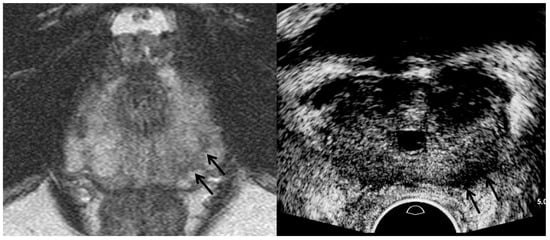

3. TRUS Imaging Features

| TRUS Features | Peripheral Cancer | Transition Cancer | ||

| Insignificant Cancer | Significant Cancer | Insignificant Cancer | Significant Cancer | |

| Echogenicity | Low | Lower | High | Higher |

| Size | Small | Large | Small | Large |

| Echotexture | Homogeneous | Heterogeneous | Homogeneous | Heterogeneous |

| Margin | Smooth | Irregular | Smooth | Irregular |

| Perfusion | Low | High | NA | NA |

| Hypoechoic rim | NA | NA | Clear | Unclear |